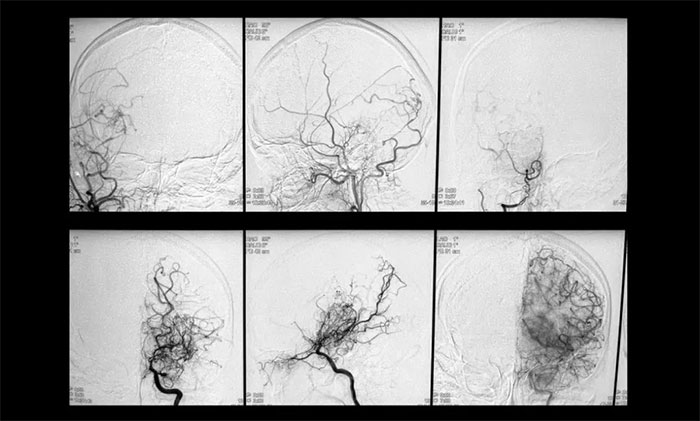

▲影像学检查符合烟雾病特征

神经外科6A病区专家团队为她完善了相关检查,结果显示:双侧颈总动脉分叉处管腔中度狭窄,右侧椎动脉纤细,异常小血管网状聚集,符合“烟雾病”典型特征。